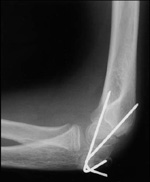

This x-ray shows a supracondylar humerus fracture that has been put into the correct position and held in place with two pins. The pins will be removed after healing has begun.

Reproduced from: Surgical management of pediatric fractures in the upper extremity, Flynn J, Sarwark J, Waters P, Bae D, Lemke L: Instr Course Lect 2003, 54: 635-645.